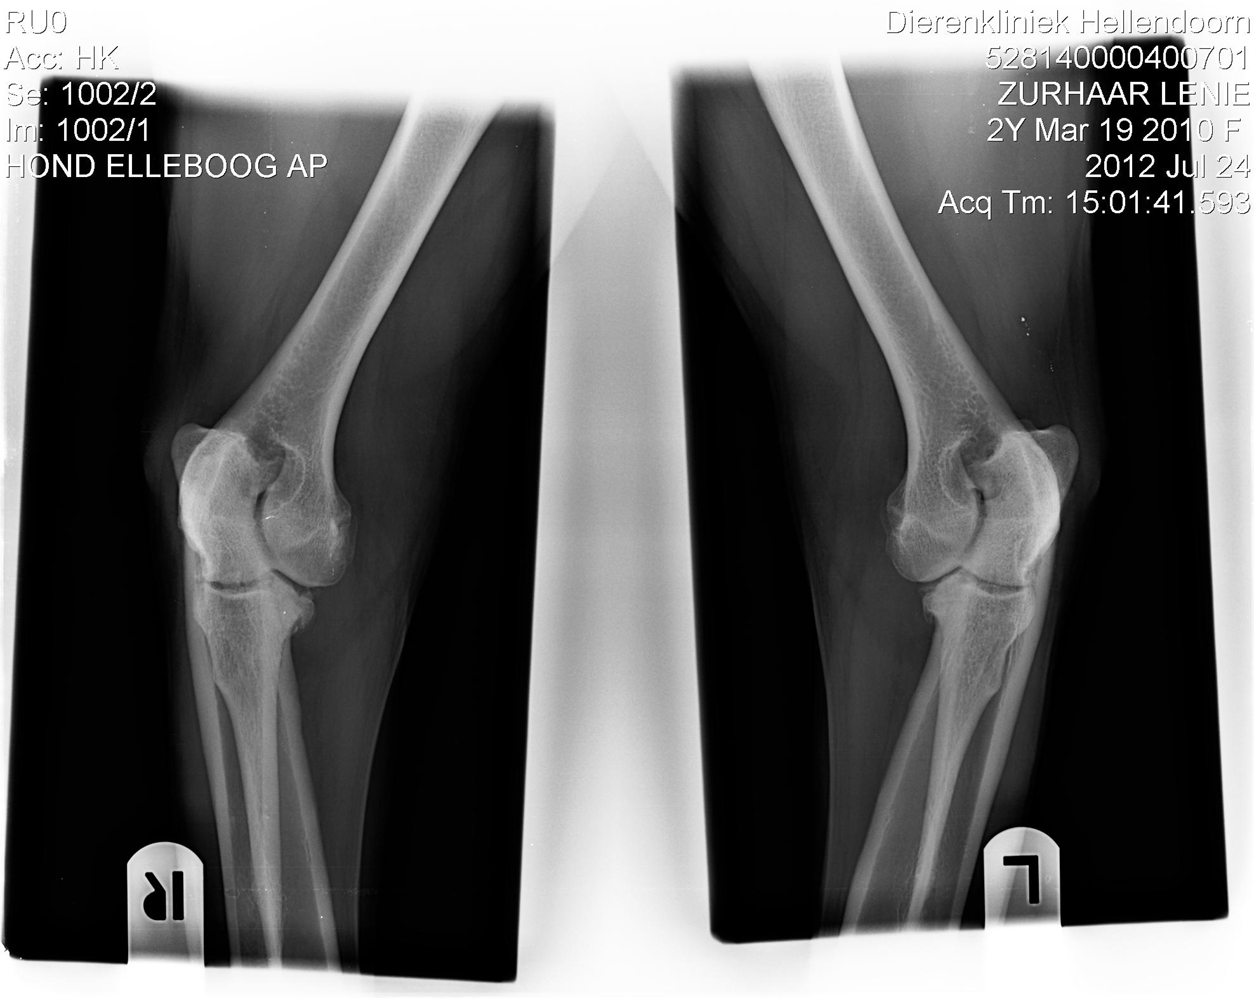

Ellenbogen

(Beide Bilder könnt Ihr anklicken um sie Euch vergrössert anzeigen zu lassen.)

Die Hüfte hat der Doc mir, wenn wir die Bilder hätten auswerten lassen wollen, mit HD 0 eingeschätzt. Bei den Ellenbogen handelt es sich nach seiner Meinung leider um eine ED 1....